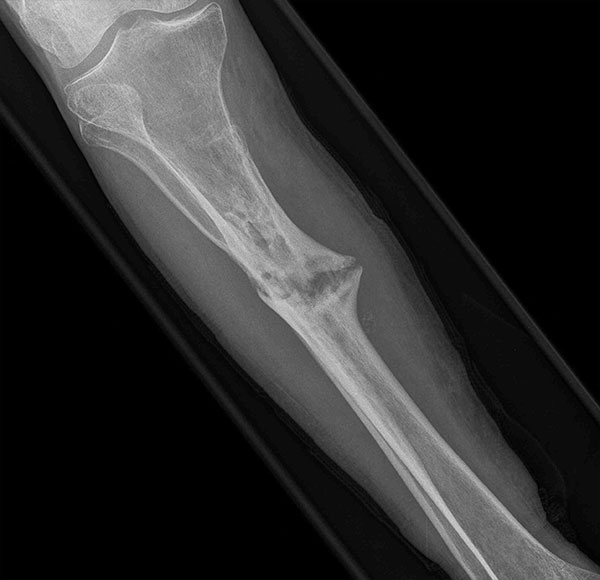

- Primary Objective Evaluate the effect of standard pain management without NSAIDs (Group 1) vs. standard pain management plus up to 6 weeks of NSAIDs (Group 2) in the treatment of tibial shaft fractures.

- Ongoing